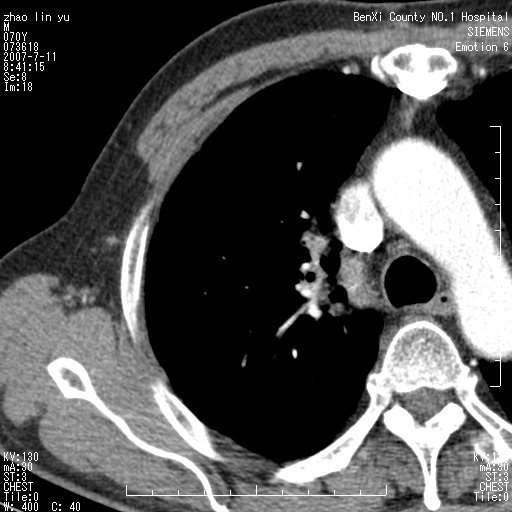

以下是引用王靖旗在2007-7-10 17:12:00的发言:[br] 男、70、咳嗽两个月,半年前换瓣手术,胸片未见异常,于昨天行x片发现右肺上野大片影,行ct扫描,这里是减薄图像,余肺正常。明天晚上会有增强扫描片,到时我会上传。[br][br] 冠状位请大家细看,应该是有意义的,[br][br] 请大家先看平扫发表意见。[br][br]

以下是引用zhangzhongshou在2007-7-10 21:43:00的发言:[br]右肺上叶周围型肺癌,以孤立型细支气管肺泡癌可能性大。